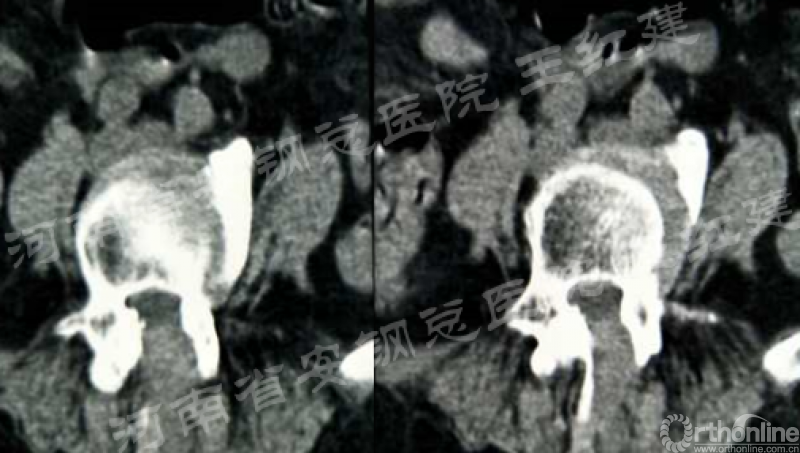

应用通道技术进行植入融合时,首先要更换工作套管,通过枪钳、抓钳的应用处理椎间盘,接着进行自体骨或同种异体骨及cage植入,并通过C臂透视确定试模型号放置融合器,最终完成植骨融合。

镜下观察椎间处理后终板软骨

镜下植骨